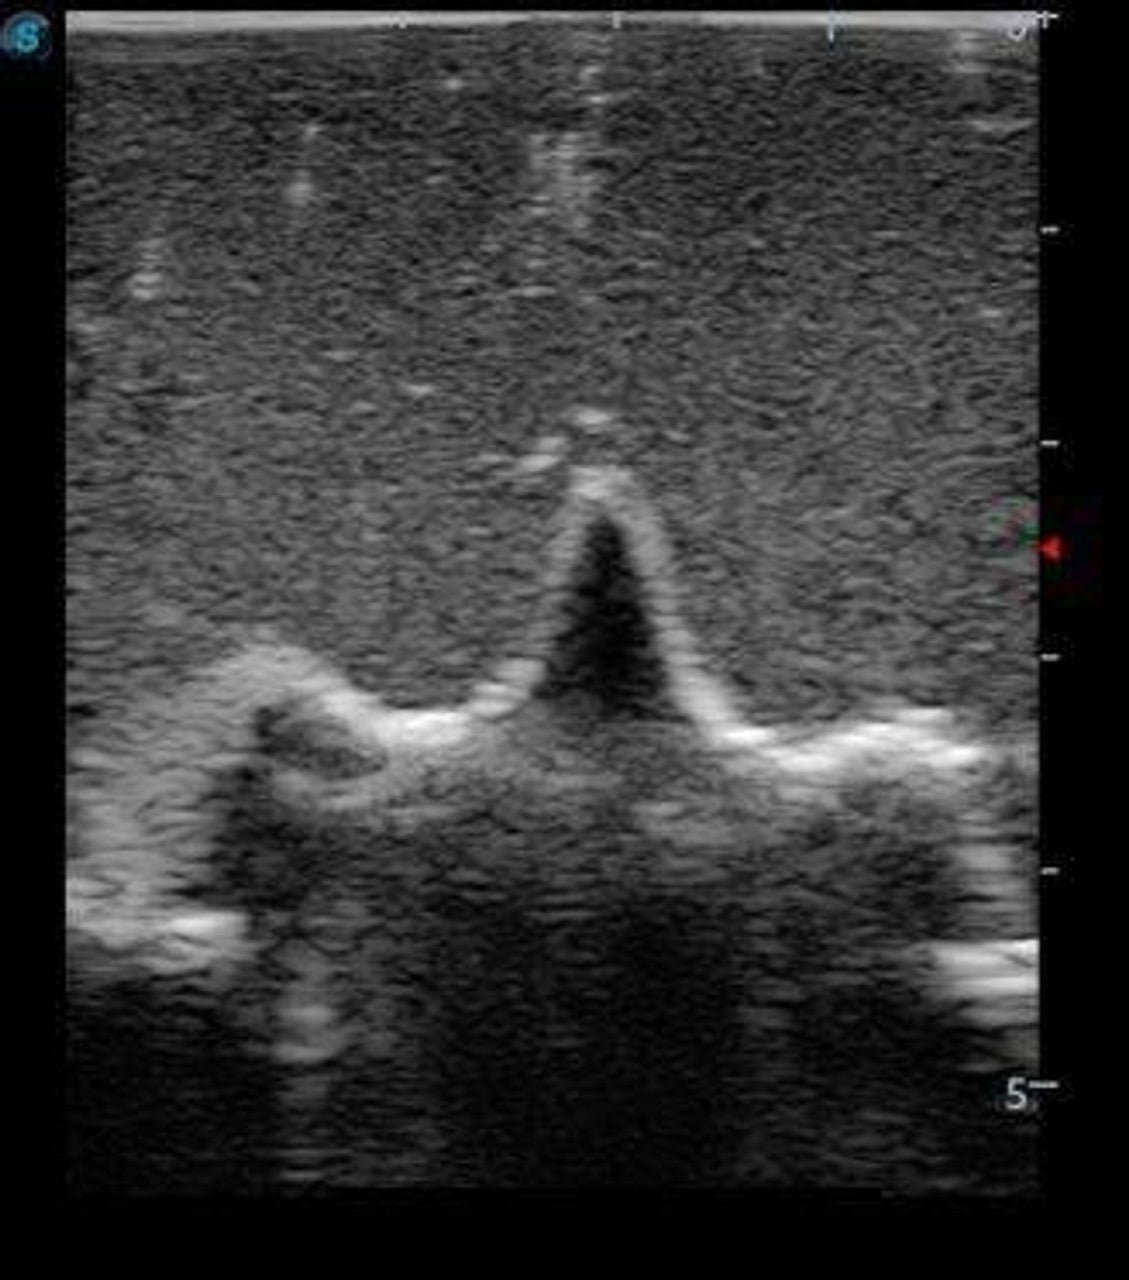

This model is an ideal choice for ultrasound-guided pediatric lumbar puncture training with true-to-life skin feel and touch, accurate anatomical structure as well as real clinical ultrasound images. Realistic resistance to needle tips and correct landmarks provide excellent hands-on experience.

Enhance your procedural confidence with the Anatomy Lab Adult Lumbar Puncture Training Model—an advanced simulator designed to replicate the tactile and visual experience of performing a lumbar puncture under ultrasound guidance. This model provides both anatomical accuracy and ultrasound realism, enabling learners to visualize vertebral structures, practice needle placement, and confirm accurate spinal access in real time. Bring clinical realism into your classroom or simulation lab and prepare learners for successful patient outcomes.

- Simulates ultrasound imaging of spinal structures, including vertebrae, ligaments, and epidural space.